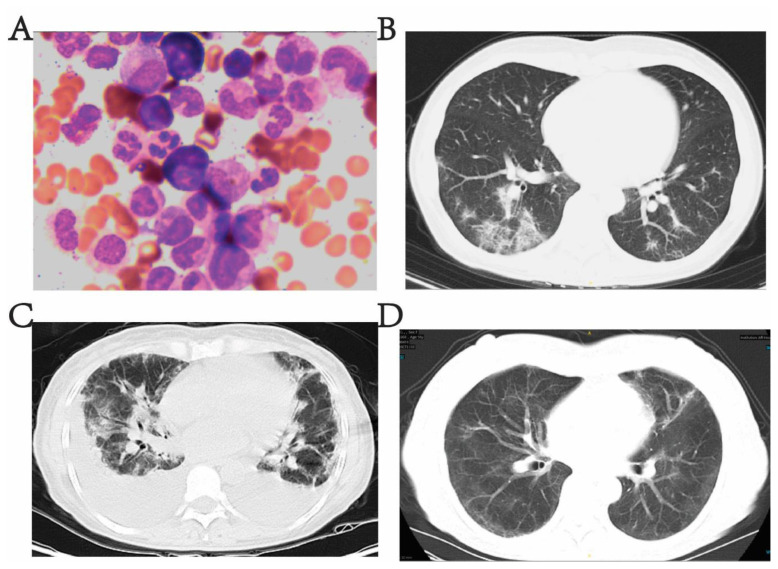

Interstitial Pneumonia Triggered by H1N1 Influenza A Virus as the Initial Presentation of Chronic Myeloid Leukemia.

由甲型H1N1流感病毒引发的间质性肺炎是慢性髓性白血病的初始表现。